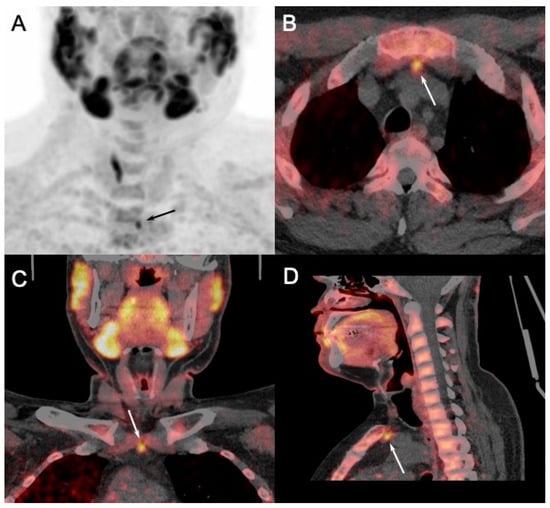

In this setting, recent studies showed not only a high global patient-based positivity rate of imaging (91% for parathyroid US and 96% for [99mTc]-MIBI scintigraphy and SPECT/CT and [18F]FCH PET/CT) [46], but also an added value of the latter imaging modality. Indeed, it was demonstrated that preoperative [18F]FCH PET/CT provides additional surgically relevant insights compared to the other imaging modalities, revealing additional pathologic glands (Figure 7), the majority of which were not detected by parathyroid US.

Moreover, in a preoperative setting, [18F]FCH PET/CT seems more accurate and useful than [99mTc]-MIBI scan in pHPT patients with positive scintigraphic results [47]. In cases of multiglandular hyperplasia, a frequent condition in patients with MEN1, the four parathyroid glands never exhibit the same intensity of uptake on [18F]FCH PET. Consequently, the supplementary information offered by [18F]FCH PET/CT could facilitate better decision-making regarding the conservation or cytoreduction of parathyroid glands based on their level of hyperfunction assessed by the SUVmax. It has also enhanced surgical exploration by targeting abnormal and ectopic locations [48] (Figure 8).

Figure 7. Discordant results of [99mTc]sestamibi parathyroid scintigraphy ((A): anterior MIP) and [18F]FCH PET/4D-CT ((B): anterior MIP; (C,E): axial and coronal fusion images; (D,F): axial and coronal 4D-CT) performed in 28-y-old MEN1 patient with recurrent primary hyperparathyroidism (PTH: 133 ng/L; calcemia: 2.70 mmol/L). [18F]FCH PET/CT confirmed scintigraphy findings (pathological left inferior gland) and detected two more hyperfunctioning parathyroids tumors (arrows, inferior right and superior left) afterwards confirmed by pathology.